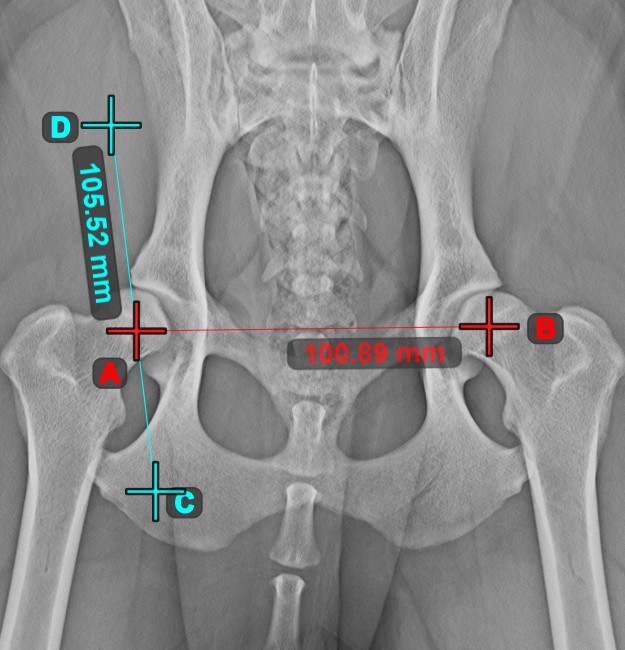

Line Measurement¶

Select the Line Measurement tool and assign it to one of the available mouse buttons. Place the start and end points on the scene or select them from already existing points on the image. The distance between the two points will be automatically

calculated by using the default calibration data, or the recalibrated data by the length calibration measurement.

Modify the start and end point by using the Select/Move Item tool. The distance between the two points will be automatically recalculated.